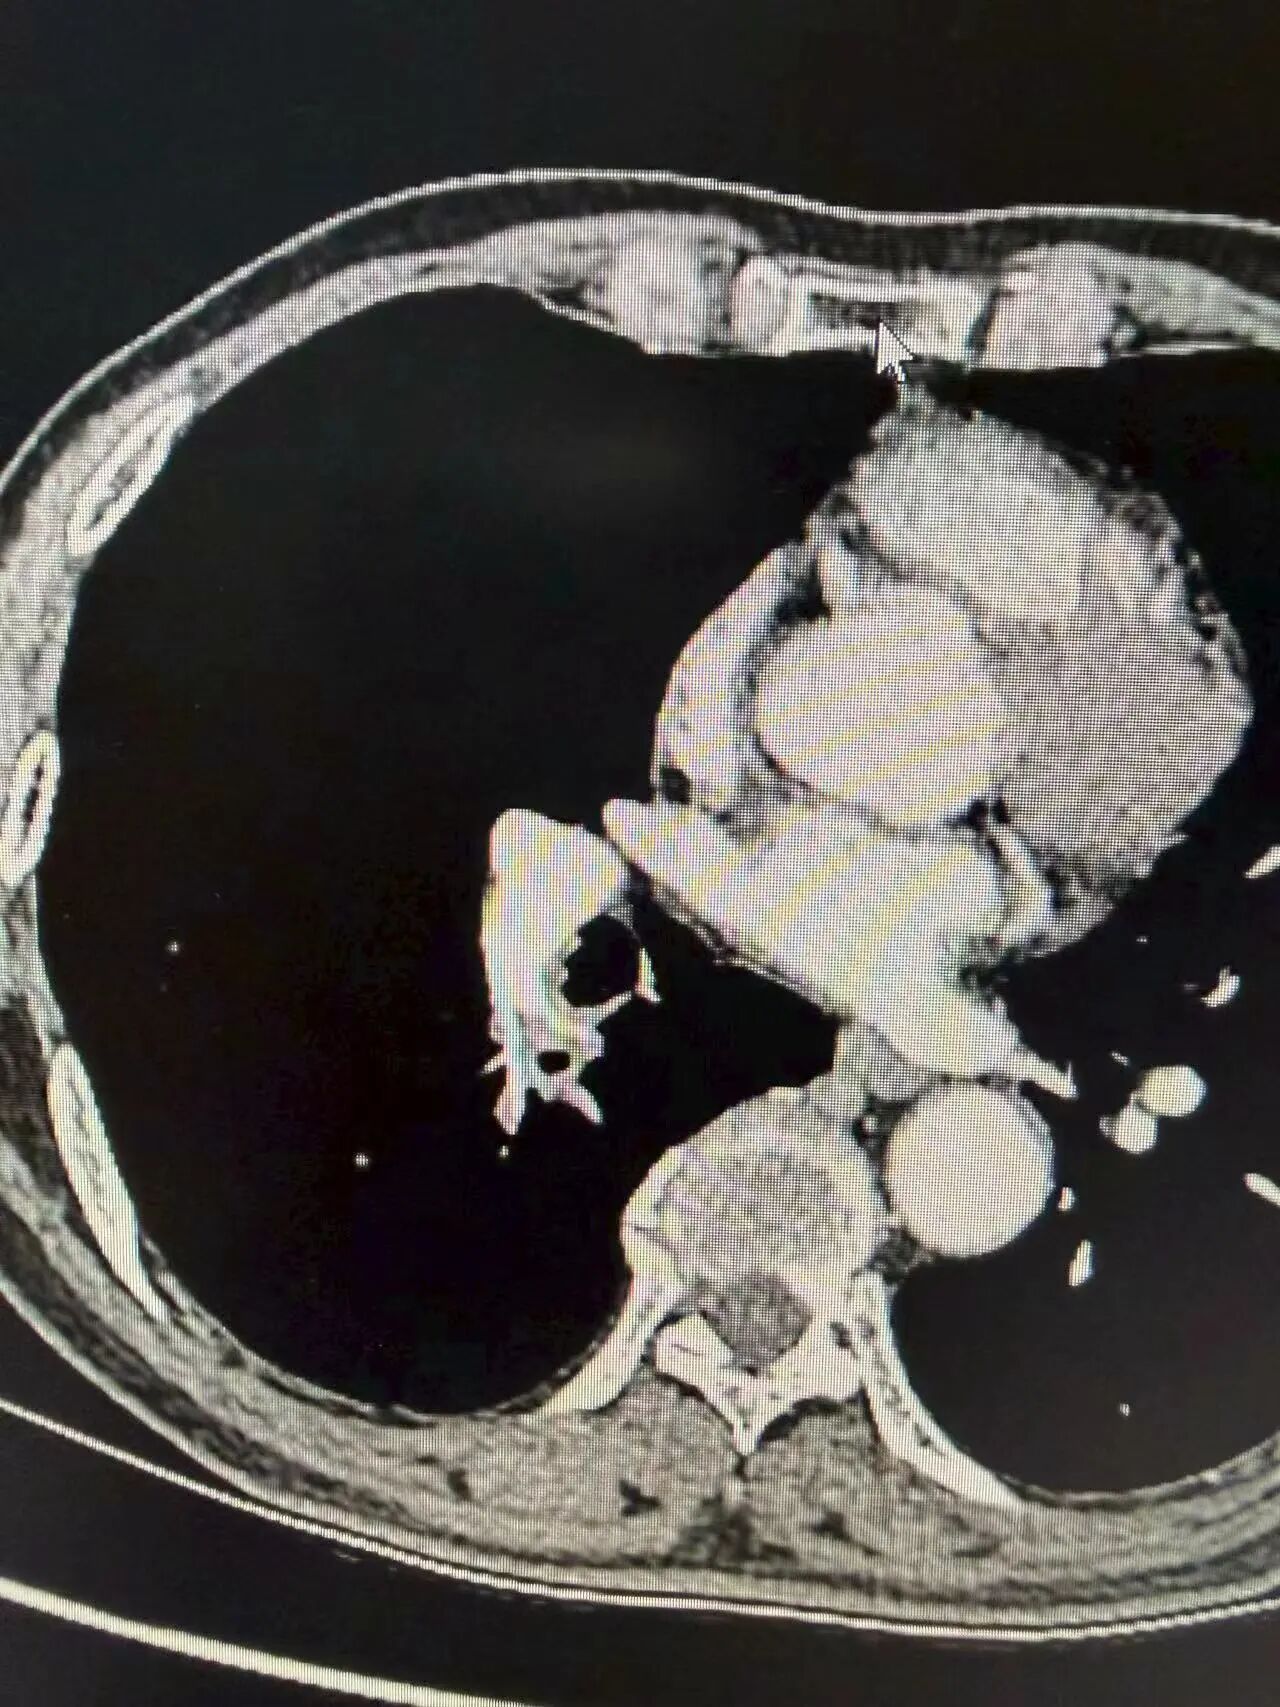

经过规范治疗后复查,效果十分显著:

经免疫联合化疗后,胸片上原右肺门占位明显缩小,阴影范围显著减小,肿瘤与周围血管界限变得清晰